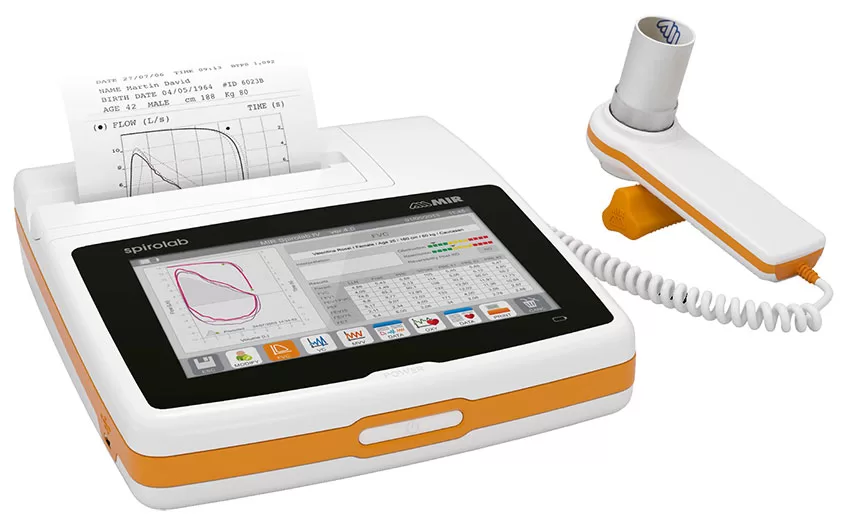

3. Teknologi Spirometer/Alat Diagnosa Kondisi Paru-Paru

Spirometer merupakan alat yang digunakan untuk diagnosa kondisi paru-paru. Kapasitas paru-paru sering dijadikan parameter kerusakan yang terjadi pada paru-paru seseorang. Proses pengukuran inilah yang dilakukan oleh alat bernama Spirometer dan proses pengukurannya diberi nama spirometri.

Untuk mengetahui kondisi paru-paru, maka Spirometer akan mengukurnya dan kemudian menampilkannya dalam bentuk grafik-grafik. Untuk menentukan baik atau tidaknya, maka grafik dari hasil pengukuran akan dibandingkan dengan grafik pada kondisi paru-paru orang normal.

Spirometer sangat penting perannya dalam dunia kesehatan paru-paru. Spirometer berperan penting pada penyakit obstruktif kronis (PPOK). Teknologi sistem pernapasan yang satu ini mampu mendiagnosa penyakit, mulai dari pertama kali penyakit itu terdiagnosa hingga selama proses pengobatannya.